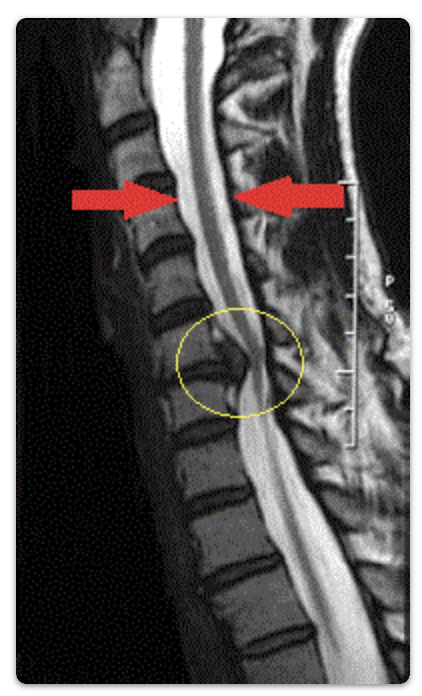

Boyun fıtığında en güvenilir teşhis, hekimin yapacağı muayenedir. Burada, hastanın şikayetleri ve hekimin muayene bulguları en önemli tanı kriterleridir. Kesin tanıya götüren tetkikler ise; MR (en sık kullanılan), bilgisayarlı tomografi, röntgen ve EMG (elektromyografi)’dir (Resim 4).

Boyun fıtığı ameliyatları önden ve arkadan girişimler olarak ikiye ayrılır. Ameliyatın önden veya arkadan yaklaşımla yapılması kararı, beyin ve sinir cerrahı tarafından sizin muayeneniz, radyolojik incelemeleriniz (MR) sonrasında verilir. Bu kararda boyun fıtığının yeri, cerrahın deneyimi gibi faktörler etkendir.